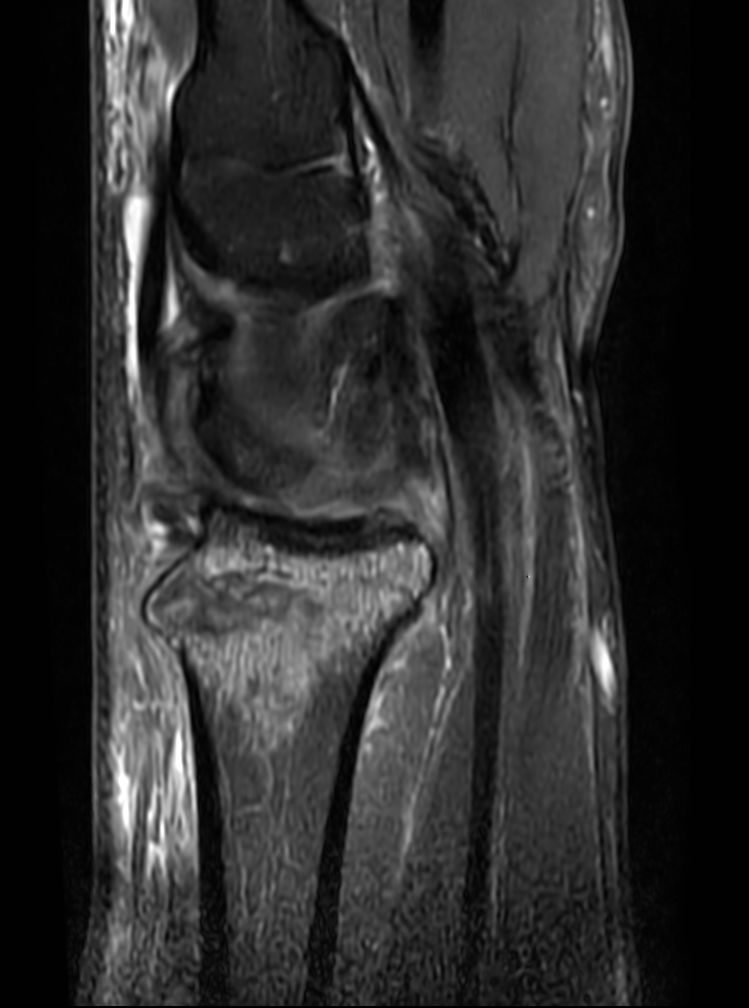

Patient with a wrist fracture. Compressed SENSE is used in all sequences, reducing the scan time while maintain equal image quality compared to scans without Compressed SENSE. 3D sequences have been added to this ExamCard with a comparable in-plane resolution but much thinner slices. Due to the shorter scan times that can be achieved thanks to Compressed SENSE, these 3D sequences could potentially replace the 2D sequences providing more confidence in making the diagnosis.

2D Sagittal PDw SPAIR